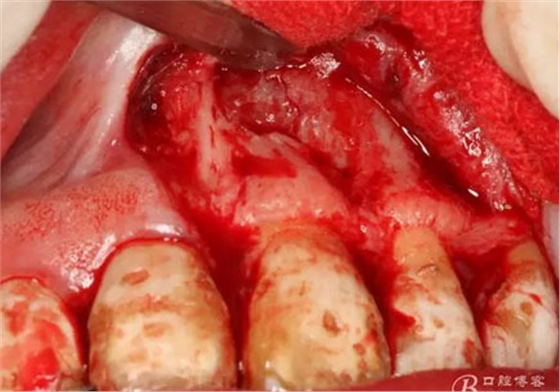

圖10.翻開粘膜瓣發(fā)現(xiàn)有唇側(cè)部分骨壁不規(guī)則缺損。

圖11.逐漸去骨薄如蟬翼的骨壁,暴露出完整的囊壁